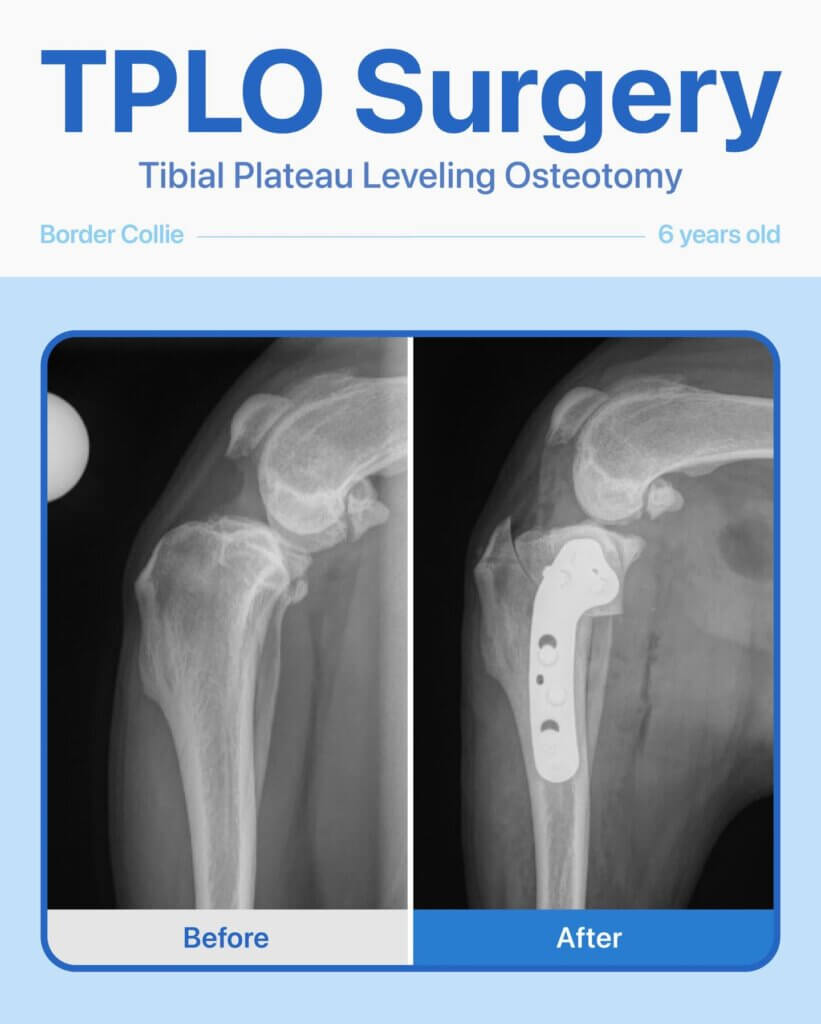

This 6-year-old female Border Collie came to us for a second opinion after showing persistent limping and reluctance to put weight on her back left leg. She had already been evaluated at another hospital, but her family wanted to explore all options.

After radiographs and a thorough orthopedic exam, our team diagnosed a torn cranial cruciate ligament (CCL). To restore stability to her knee and help her return to an active, pain-free life, TPLO surgery was recommended.